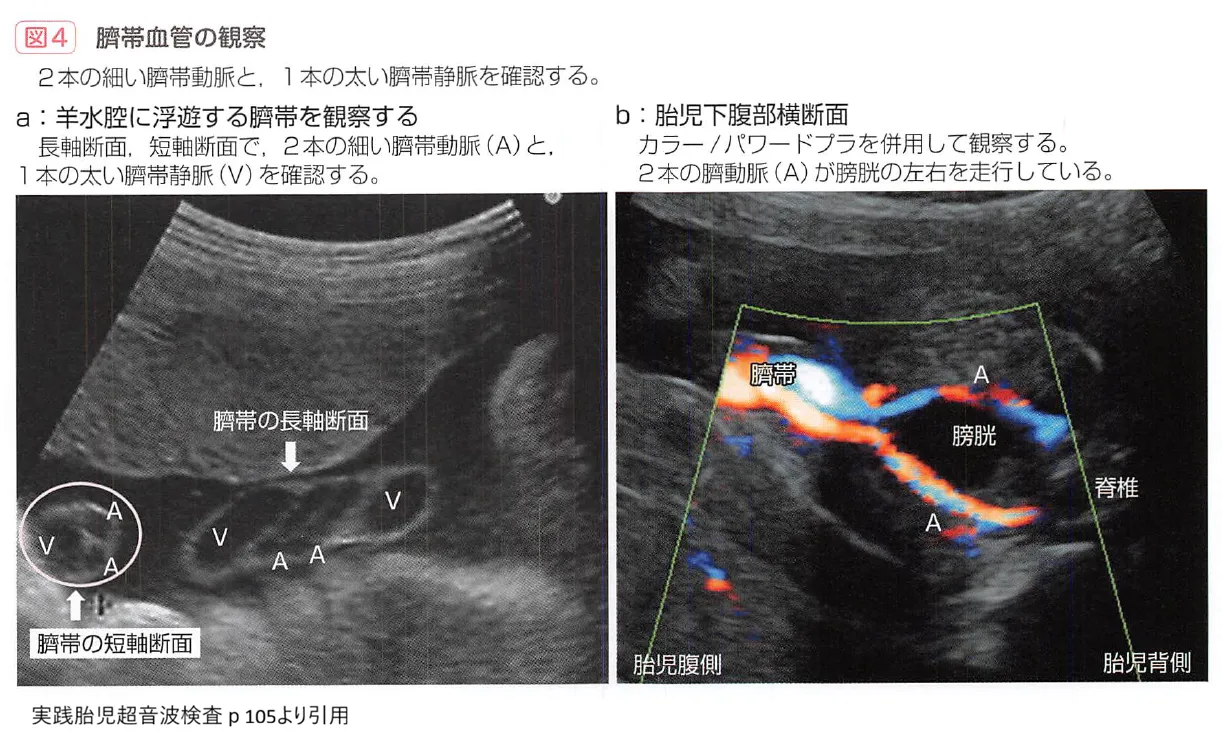

2. 単一臍帯動脈(SUA)

通常、へその緒には2本の動脈と1本の静脈がありますが、動脈が1本しかない状態を指します。ダウン症を含む染色体異常や、心臓・腎臓の奇形を合併するリスクが上昇します。